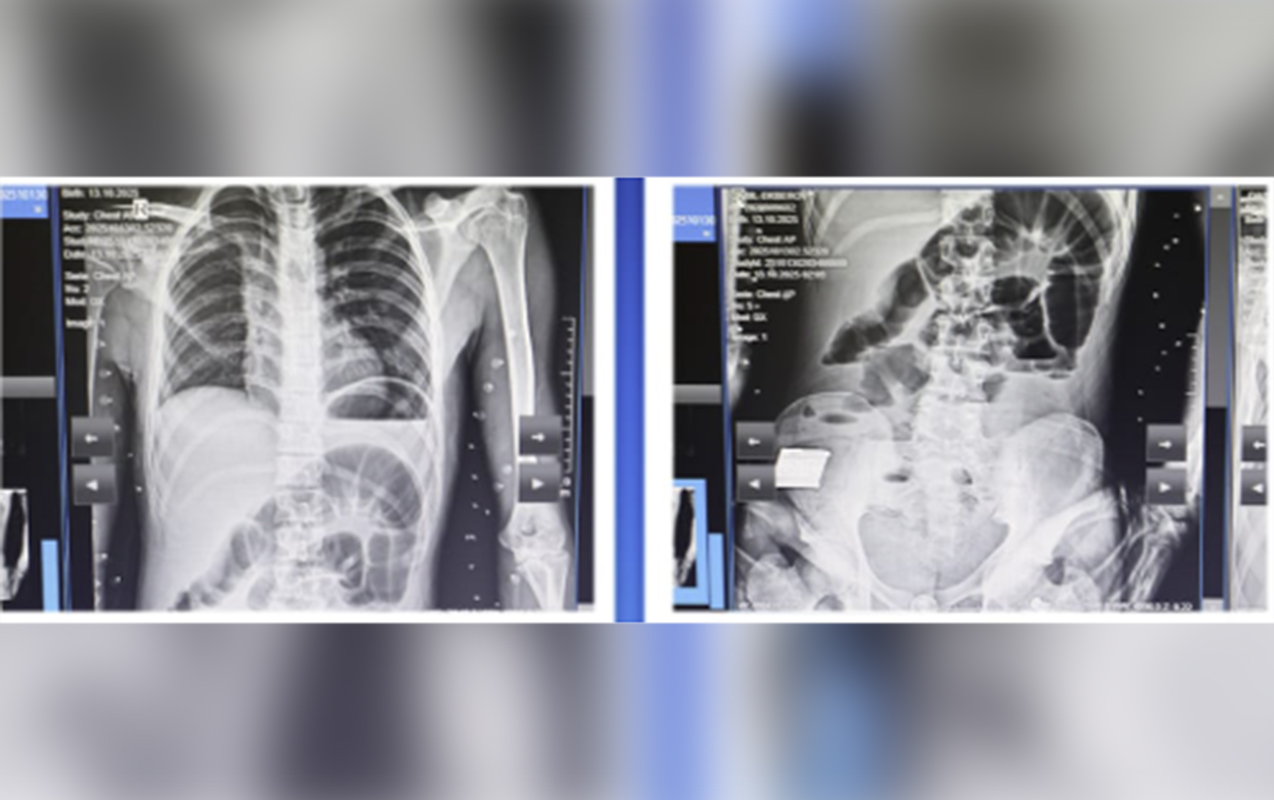

Bildirilib ki, oktyabrın 14-ü 2008-ci il təvəllüdlü yeniyetmə qarın nahiyəsində kəskin ağrı, ürəkbulanma, təkrarlanan qusma və hipertermiya şikayətləri ilə Kliniki Tibbi Mərkəzin Təcili və təxirəsalınmaz tibbi yardım şöbəsinə gətirilib: “Müayinələr nəticəsində xəstəyə peritonit diaqnozu qoyulub və əməliyyatönü hazırlıqdan sonra təxirəsalınmaz cərrahi müdaxilə aparılıb. Həkimlər tərəfindən nazik bağırsaq seqmentinin rezeksiyası, yoğun bağırsağın defektinin tikilməsi əməliyyatı icra olunub.

Əməliyyat zamanı nazik bağırsaqda, iliosekal küncdən 70-80 sm məsafədə, iki yerdə deşici (perforativ) zədələnmə müəyyən olunub. Bu perforasiyalara səbəb bağırsaq mənfəzində yerləşən iti və sərt yad cisim taxta parçası olub. Bundan əlavə, yoğun bağırsaqda da perforativ dəlik və bütün nazik bağırsaq boyunca mənfəz daxilində müxtəlif ölçülü, iti uclu, sərt yad cisimlər aşkarlanıb”.